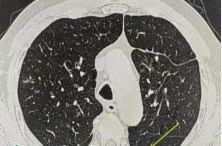

这种真菌感染的症状往往很隐蔽,患者多表现为咳嗽、咳痰、胸痛,很容易被当作普通的肺炎或咽喉炎来处理。肺部影像学也缺乏特征性改变,多类似于肺炎、肺结核或肺脓肿病变。正是因为这些症状、检查缺乏特异性,很多患者像张大爷一样,在确诊前经历了漫长的求医过程。